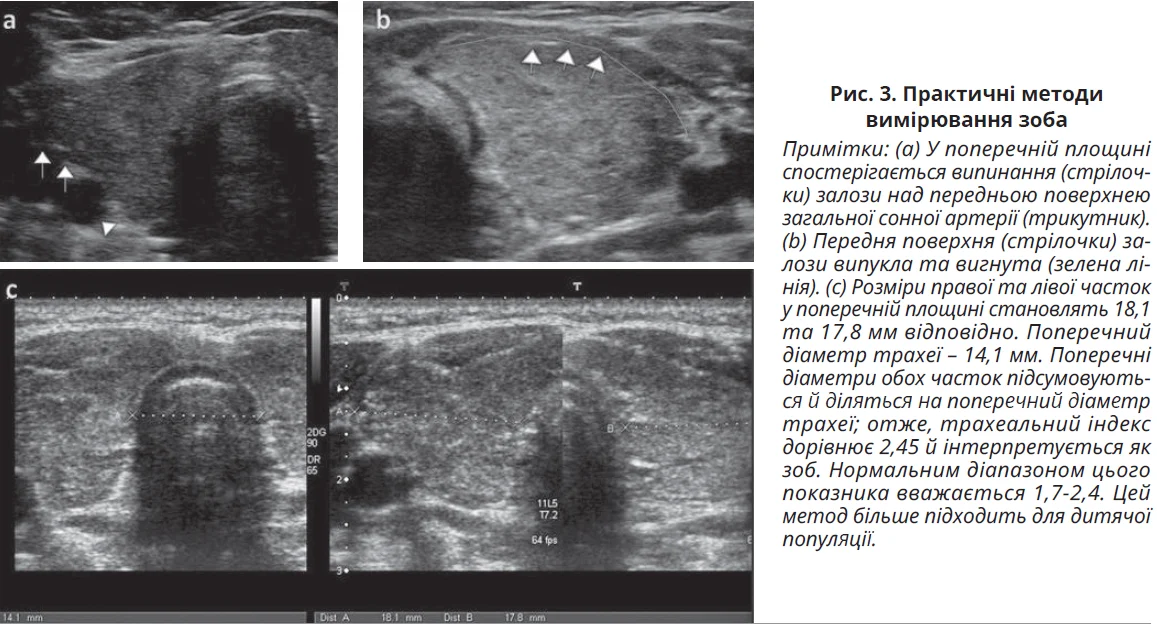

Нормальний розмір ЩЗ варіює залежно від статі та зросту пацієнтів. У дорослих у нормі розміри кожної частки становлять приблизно 5×2×2 см у сагітальному, передньо-задньому та поперечному вимірах відповідно. Перешийок вимірюється в поперечній площині, його верхня межа дорівнює 0,3 см. За перевищення цих розмірів вважається, що ЩЗ збільшена, тобто наявний зоб. Окрім вимірювань, на зоб указують опуклість передньої поверхні часток (у нормі передня поверхня зазвичай симетрична та має плаский або увігнутий край і виступ залози над передньою поверхнею загальної сонної артерії в поперечній площині. ЩЗ у нормі може виступати над поверхнею сонної артерії без збільшення; в цьому випадку важлива форма переднього контуру. Якщо вона пласка чи увігнута, зоб не діагностується. У дітей форма та контур залози є важливішими, ніж її розмір; ці показники використовуються для характеристики росту залози. При розрахунку об’єму ЩЗ використовують формулу еліпсоїда: ширина × довжина × висота × 0,523. Практичнішим методом визначення розміру ЩЗ є трахеальний індекс, що розраховується шляхом поділу суми поперечних діаметрів обох часток на поперечний діаметр трахеї. Нормальним діапазоном цього показника вважається 1,7-2,4. Практичні методи вимірювання зоба показано на рисунку 3.